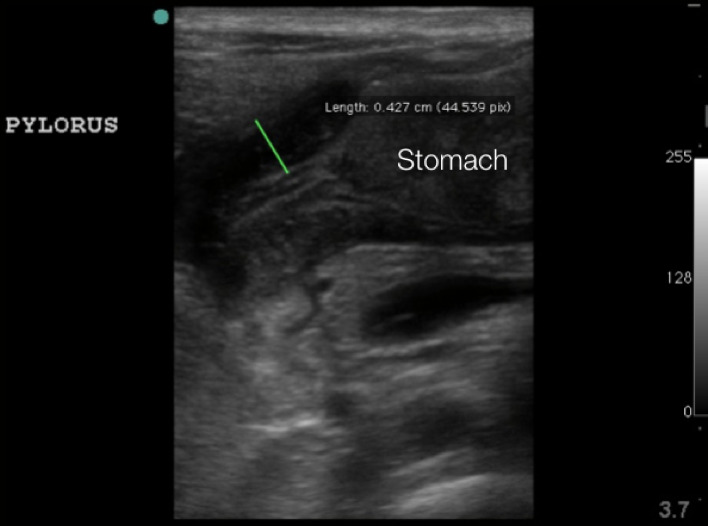

- Thickness of the pyloric muscle can be measured in the long or short axis view

- Figure 6. Hypertrophied pyloric muscle in long axis measuring 4.3mm